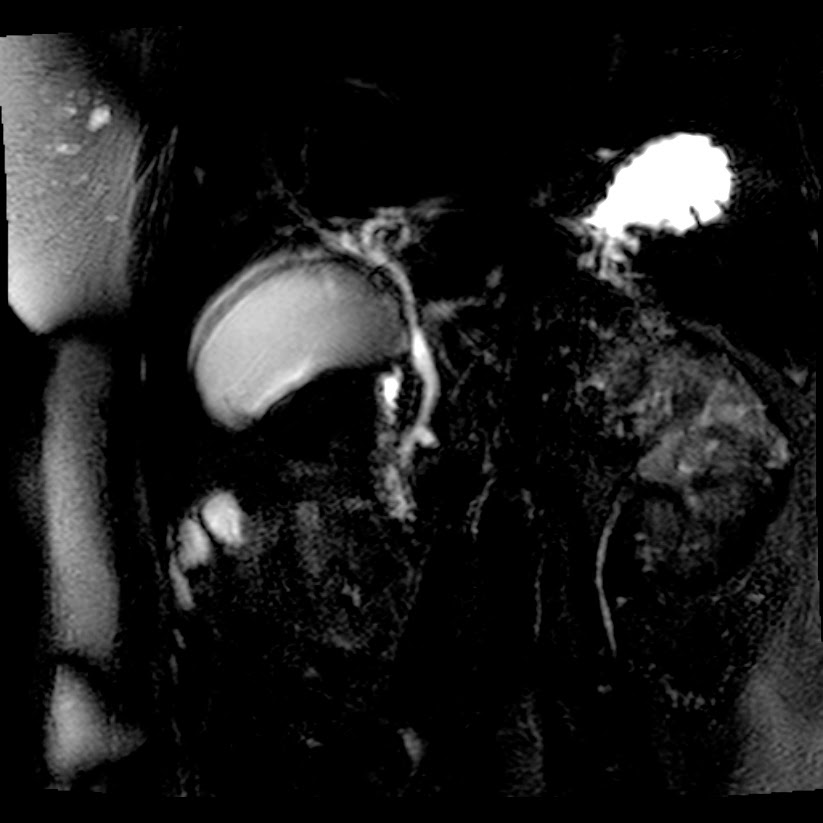

Respuesta al Caso #6

Segmento lateral del lóbulo medio